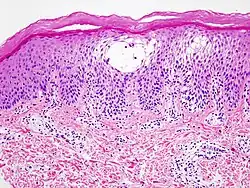

histologischer Schnitt

Die Symptome treten überwiegend an den Handflächen, Fingerseitenflächen und Fußsohlen auf. An den betroffenen Hautarealen finden sich kleine, wasserklare und meist stark juckende Bläschen. Bei einer histologischen Untersuchung des Gewebes zeigen sich schwammartige (spongiotische) Bläschen innerhalb der Oberhaut (Epidermis). Die betroffene Haut ist meist gerötet. Die Hautveränderungen können schubweise auftreten oder sich über längere Zeit hinziehen. Die Bläschen können aufplatzen und beginnen dann zu nässen, wobei es zu Infektionen kommen kann. Bei der Abheilung schuppt sich die Haut. Bei längerer Erkrankungsdauer verhornen die betroffenen Hautstellen und es bilden sich blutende Rissstellen (Rhagaden).